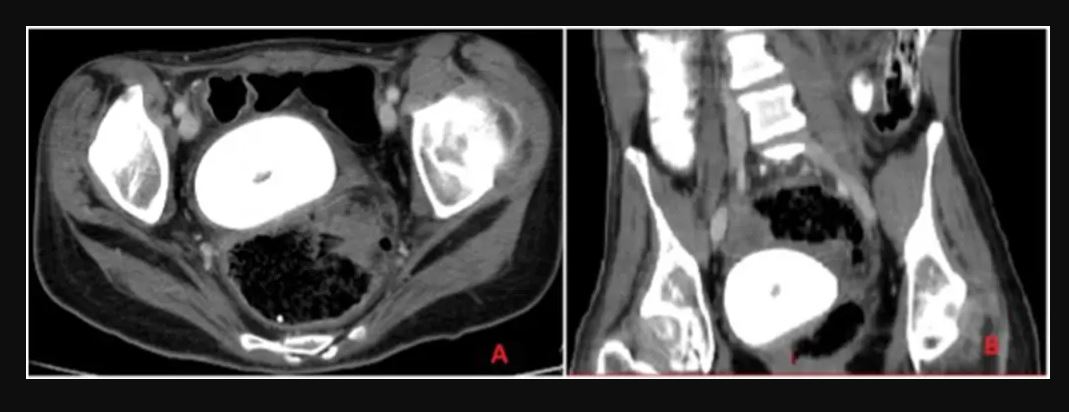

Η αξονική τομογραφία της λεκάνης και της κοιλιάς αποκάλυψε τον “ένοχο”. Οι κολπικές πέτρες «σχηματίζονται από την εναπόθεση ανόργανων αλάτων από στάσιμα ούρα μέσα στον κόλπο», σύμφωνα με μια ερευνητική εργασία του 2019 που δημοσιεύτηκε στο Medicine . Λόγω της σπανιότητας της πάθησης, είπαν οι ερευνητές, έχει γίνει συχνά λανθασμένη διάγνωση στο παρελθόν.

Ο σχηματισμός ήταν τόσο μεγάλος που πίεζε την κύστη της γυναίκας, κάτι που οδήγησε σε ακόμη μεγαλύτερη διαρροή ούρων.